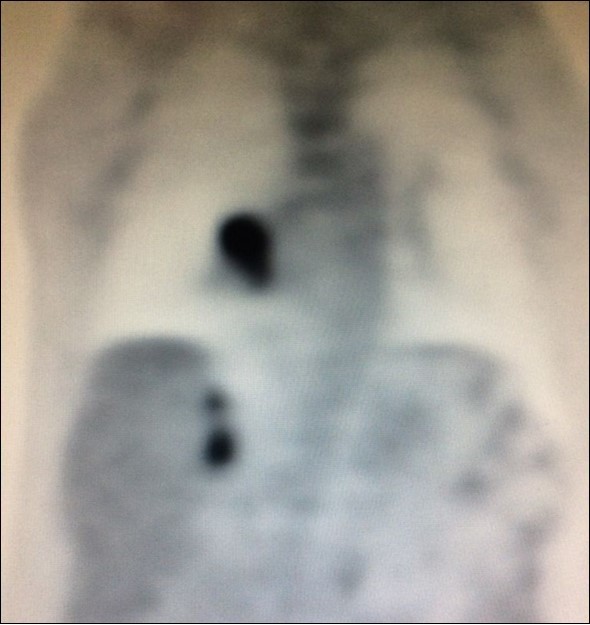

There is limited understanding of the efficacy of surgical resection because of low incidence of isolated adrenal metastasis in patients with stage IV NSCLC. Some series showed that the time from diagnosis of primary lung cancer diagnosis of adrenal metastasis - disease-free interval (DFI) – is a prognostic factor6. Synchronous metastases (Figure 4), defined as a DFI of 6 months or less, has been associated with a poor prognosis.

Figure 4.PET CT showing simultaneous uptake on right lung mass and 2 ipsilateral adrenal nodules.